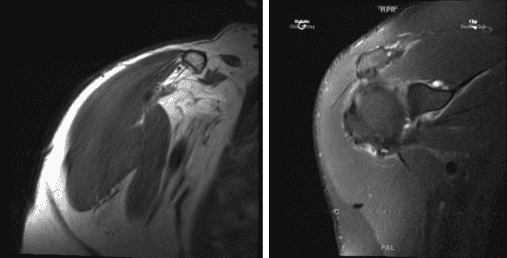

After a week, the patient presented his MRI. Impression as follows: Mild-moderate supraspinatus and infraspinatus tendinosis, with mild bursal fraying of junctional-zone fibers. Small, low-grade interstitial tear within the inferior subscapularis tendon.

Background mild-moderate subscapularis tendinosis, with low-grade intrasubstance fissuring superiorly. Complete versus near-complete rupture of the intra-articular segment of the biceps tendon, with retraction of the distal tendon stumps of the bicipital groove. Additional shortness and segment split tearing the extra-articular biceps tendon.

Short stump of the biceps anchor remains attached to the superior glenoid margin. Posterosuperior labral tearing (9-1:00, associated with a large Para labral cyst that tracks medially and anterosuperiorly; dominant cyst locule is situated anterior to the supraspinatus muscle. Moderate acromioclavicular joint arthrosis. Mild subacromial bursitis. Mild subacromial spurring.